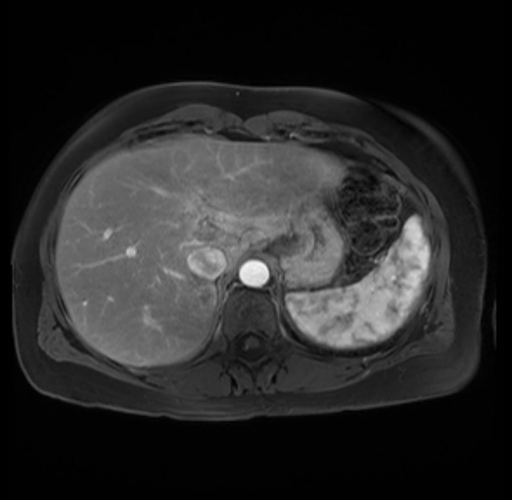

Imaging Analysis

Look through the patient's CT scan to identify any areas of concern for the necessary procedure.

Based on your CT findings, which issue(s) are present and would give reason for "planned slowing down moment(s)" in this case?